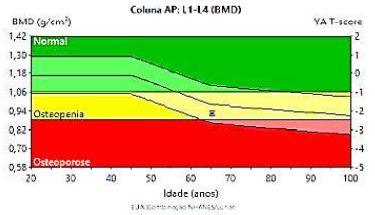

Sobre o exame a seguir pode-se afirmar:

Assinale a alternativa correta.